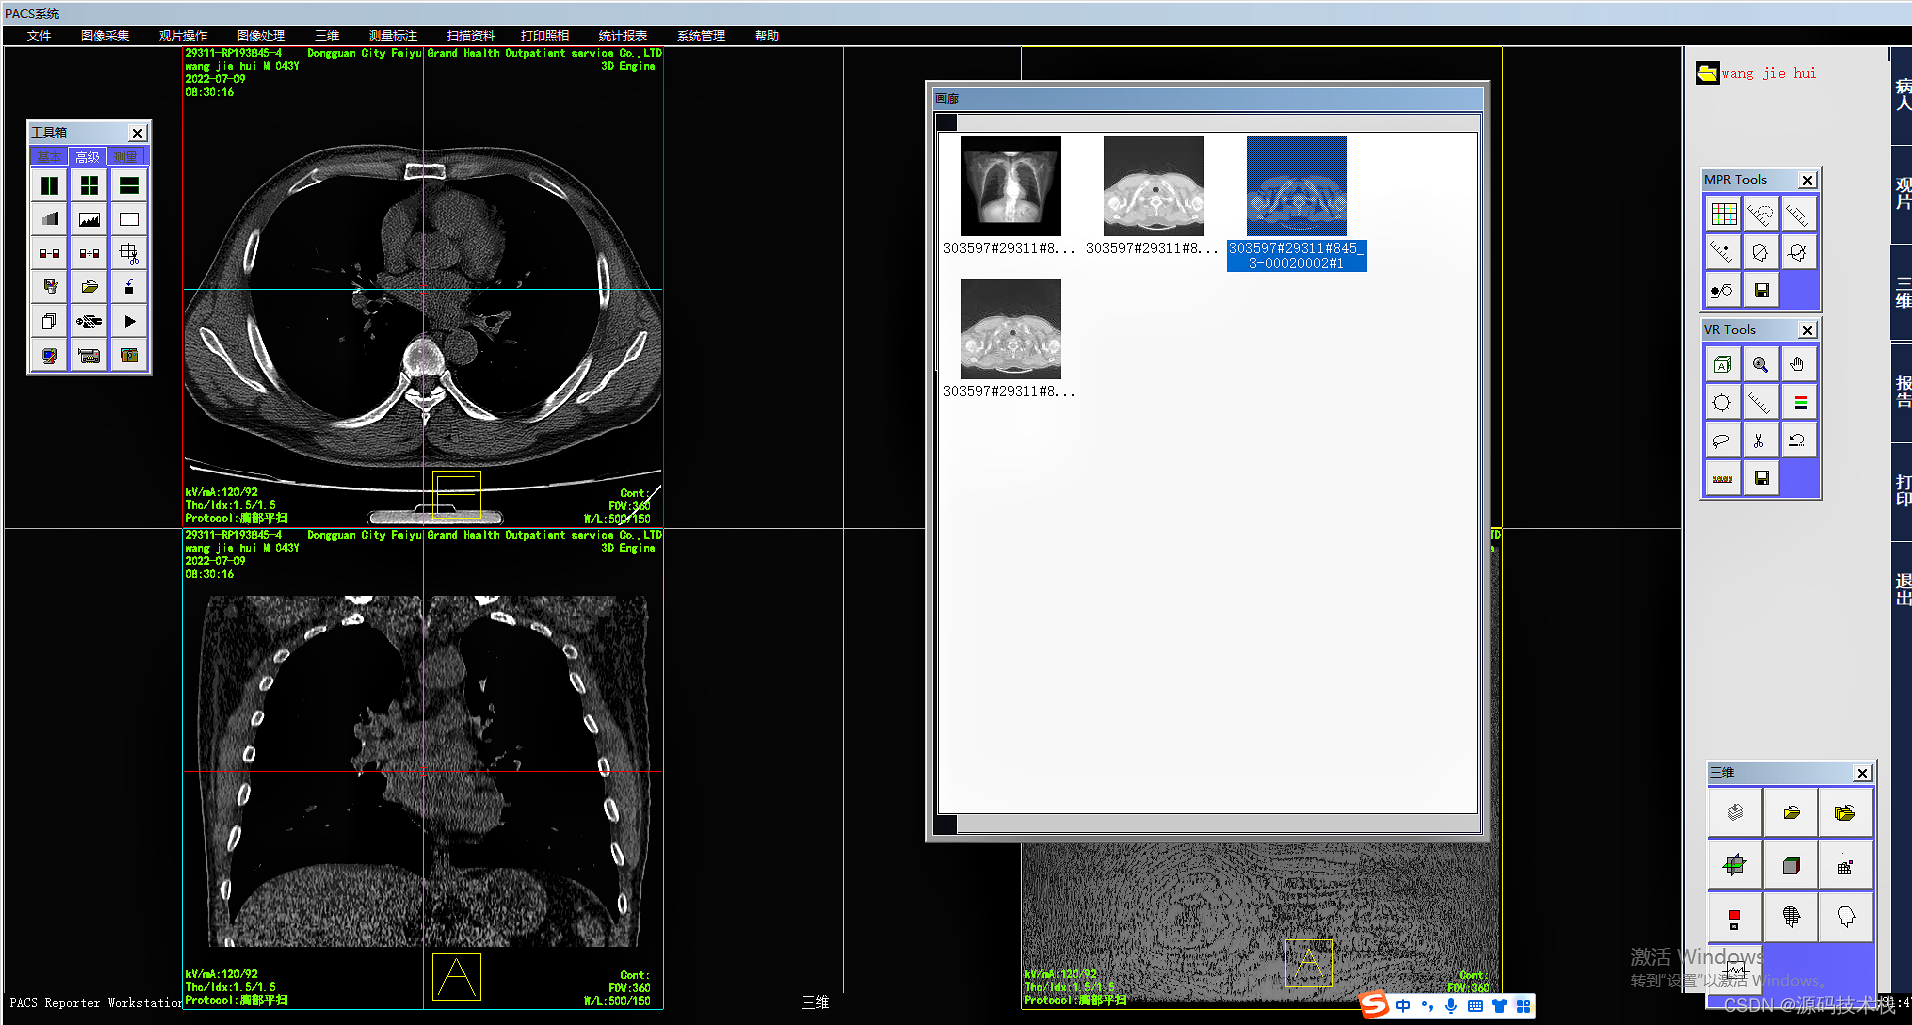

影像查阅

系统采用DICOM和非DICOM格式获取影像数据,以通讯方式采集影像原始DICOM数据;

支持静态和动态影像数据采集;

支持透视采集和曝光采集等多种采集方式;

支持非DICOM影像设备的影像数据转化为DICOM标准的数据。

支持读取DCMDIR文件,显示并打开相关联的DICOM文件;

显示多种图像文件格式,并能转换成DICOM格式;

支持多屏和竖屏显示;支持动态影像电影方式回放、逐帧漫游和冻结;

支持同屏显示多幅影像,自定义显示矩阵;

支持同屏显示同一患者在不同检查设备检查的多个动态电影图像;

支持检查模式、比较模式和打印模式的图像显示;

支持多屏显示同一患者的不同序列图像或不同患者的图像;

支持同屏分格显示患者不同体位和不同设备的影像;

支持不同患者间的影像对比。

图像后处理与重建

·MPR\CPR(三维多平面重建)

·VRT(三维容积重建)